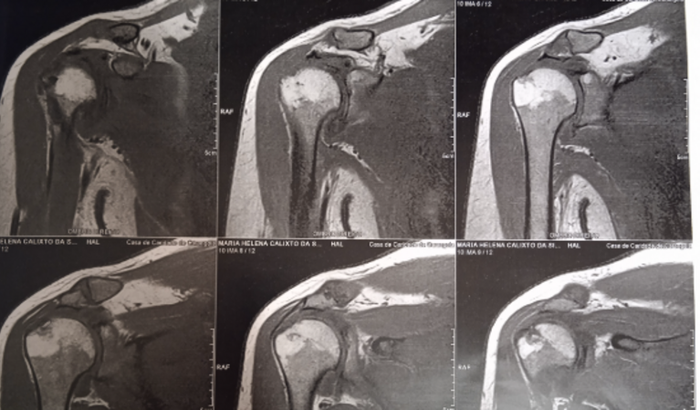

Eu sou a Maria Helena, e meu ombro direito foi diagnosticado rompimento de tendão total e posso a qualquer momento perder o movimento e se passar mt tempo não vai ter como consertar o tendão e vai ter o movimento de osso com osso do braço com a clavicula a cirurgia custa em torno de 15 a 18 mil reais e eu sou doméstica ganho um salário mínimo, e não tenho condições de pagar, por isso peco a tds q puderem me ajudar, que Deus lhe dê em dobro.